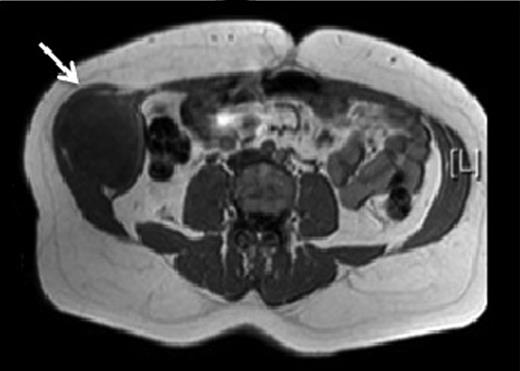

A 43-year-old Caucasian female presented to her General Practitioner in April 2012 with a 2-year history of a firm, painful swelling in the right flank. MRI revealed a 5.0 × 6.0 × 7.0 cm enhancing lesion with areas of necrosis, which was invading the antero-lateral abdominal wall (Fig. 1 ). With radiological features highly suggestive of a sarcoma, she underwent an ultrasound-guided biopsy, which classified the mass as a borderline myoepithelial tumour. The patient underwent an uncomplicated resection of the mass, which left a 10 × 10 cm right-sided antero-lateral abdominal wall defect. The defect was repaired using a Biodesign® biological graft. Initially, a layer of the biological mesh was used to cover the intact peritoneum with attachments cranially to the ribs and inferiorly to the right iliac crest. The external oblique was mobilized to partially cover the mesh, and a further layer of the biological mesh attached over it with Ethilon™ (Fig. 2). The patient had an uncomplicated postoperative recovery. The tumour histology revealed a 6.5 × 6.0 × 5.5 cm myxoid mass; immunohistochemistry analysis favoured a benign/borderline myofibroblastic tumour. At 24-month follow-up, she had good wound healing with a small area of paraesthesia inferior to the scar. An MRI showed good graft incorporation and no evidence of disease recurrence or hernia (Fig. 3).

T1 MRI showing a soft tissue abdominal wall tumour involving external oblique, internal oblique and transversus abdominis and not involving the peritoneum (arrow).